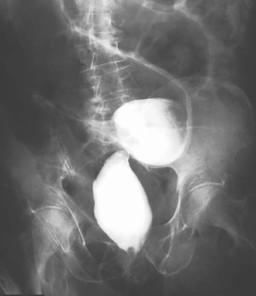

Aspect en bec de oiseaux

d'une volvulus du colon sigmoide . L'opaque

hydrosoluble arrete au point de volvulus . L'anse de

volvulus est tres dilate en forme de " grain de cafe

" . Image radiologique de lavement opaque

hydrosoluble . |

Occclusion du colon du

adenocarcinoma du colon gauche : Image d'une stenose

courte irregulier d'une cancer du colon gauche

|